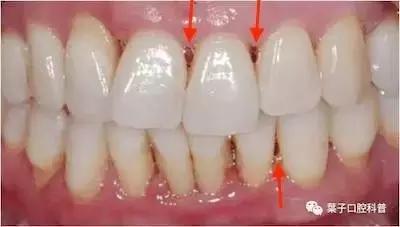

如果两颗牙齿之间的牙龈乳头退缩(牙龈萎缩),就会造成两颗牙齿之间下方出现空隙,食物就比较容易在嘴唇、脸颊和舌头的运动作用下,水平地进入了间隙,造成了“卡肉”的现象。